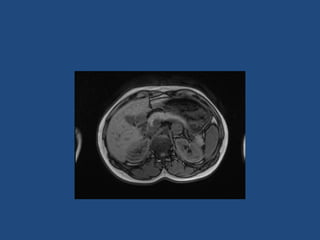

Adrenal imaging

Imaging

•

>6cm high suspicion of malignancy

3-6cm repeat imaging in 3-6M

Delayed washout on contrast is suggestive

most are often inhomogeneous, irregular

margins

• Look for invasion of IVC

• Always do CAP and consider bone scan and

pet if in doubt

• Don’t ever biopsy (tumour spill)

Imaging • • • • >6cm high suspicionof malignancy 3-6cm repeat imaging in 3-6M Delayed washout on contrast is suggestive most are often inhomogeneous, irregular margins • Look for invasion of IVC • Always do CAP and consider bone scan and pet if in doubt • Don’t ever biopsy (tumour spill)